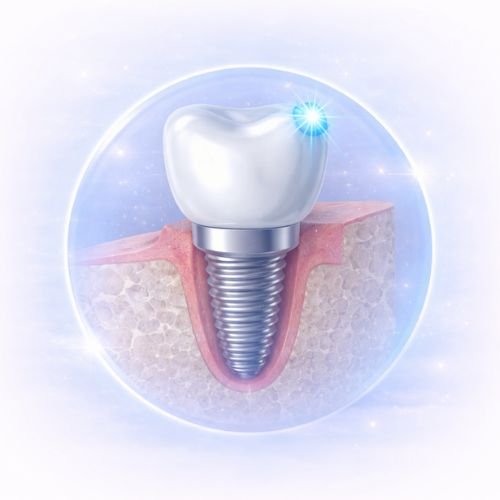

What Are Dental Implants?

Dental implants are titanium posts surgically placed into the jawbone to replace missing tooth roots. Once healed, a custom crown is attached to restore the appearance and function of a natural tooth.

At AB Dentalogic, the top dental clinic in Newtown, dental implants are planned using 3D imaging and guided surgical techniques for maximum accuracy and comfort.

Step 2 – Implant Placement

The titanium implant is placed into the jawbone under local anesthesia.

Step 3 – Healing & Osseointegration

The implant fuses naturally with the bone over 3–6 months.

Step 4 – Crown Placement

A custom-made crown is attached for natural appearance and function.